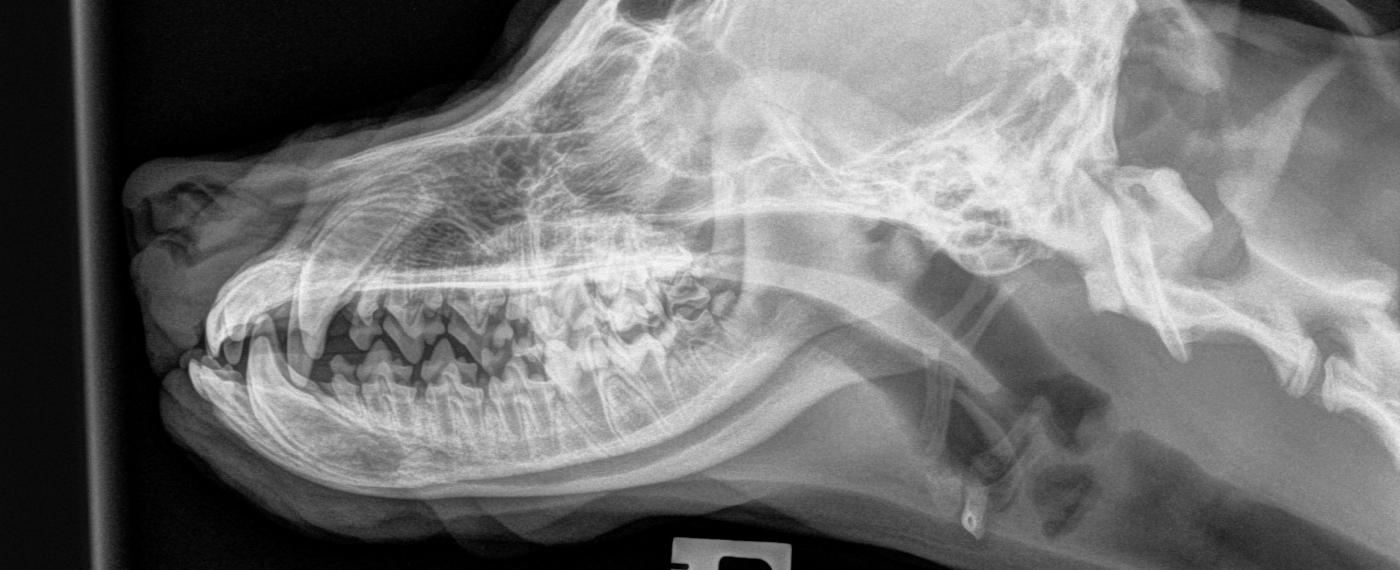

Projection Veterinary Definition . To aid with radiographic interpretation, radiograph presentation is standardized.4. The following terms are used to describe the position of individual body parts in relation to each other or to a body plane or axis. Upon completion of chapter 12 of this text, the reader should be able to do the following: in this first of two articles on radiographic positioning, we provide an overview of the principles and guidelines. Radiography in veterinary medicine is highly popular due to its low cost, ease of use, rapid image yield, and availability in most veterinary practices. this book uses the standard method for naming radiographic projections approved by the american college of veterinary radiology (1).

The following terms are used to describe the position of individual body parts in relation to each other or to a body plane or axis. To aid with radiographic interpretation, radiograph presentation is standardized.4. this book uses the standard method for naming radiographic projections approved by the american college of veterinary radiology (1). Upon completion of chapter 12 of this text, the reader should be able to do the following: in this first of two articles on radiographic positioning, we provide an overview of the principles and guidelines. Radiography in veterinary medicine is highly popular due to its low cost, ease of use, rapid image yield, and availability in most veterinary practices.